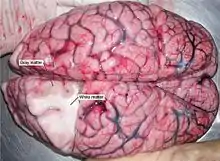

White and gray matter

Microscopically, there are differences between the neurons and tissue of the CNS and the peripheral nervous system (PNS). [11] The CNS is composed of white and gray matter.[9] This can also be seen macroscopically on brain tissue. The white matter consists of axons and oligodendrocytes, while the gray matter consists of neurons and unmyelinated fibers. Both tissues include a number of glial cells (although the white matter contains more), which are often referred to as supporting cells of the CNS. Different forms of glial cells have different functions, some acting almost as scaffolding for neuroblasts to climb during neurogenesis such as bergmann glia, while others such as microglia are a specialized form of macrophage, involved in the immune system of the brain as well as the clearance of various metabolites from the brain tissue.[4] Astrocytes may be involved with both clearance of metabolites as well as transport of fuel and various beneficial substances to neurons from the capillaries of the brain. Upon CNS injury astrocytes will proliferate, causing gliosis, a form of neuronal scar tissue, lacking in functional neurons.[4]

The brain (cerebrum as well as midbrain and hindbrain) consists of a cortex, composed of neuron-bodies constituting gray matter, while internally there is more white matter that form tracts and commissures. Apart from cortical gray matter there is also subcortical gray matter making up a large number of different nuclei.[9]